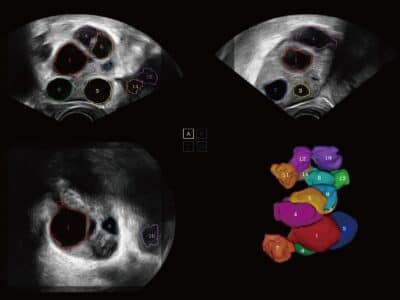

AVC Folikul

Vysoce efektivní analýza folikulů je dosažena pomocí AVC Follicle, automatického výpočtu folikulů na základě objemových dat, včetně počtu a objemu.

Folikuly jsou ve výsledcích seřazeny podle velikosti a pro lepší vizualizaci jsou zobrazeny v různých barvách.